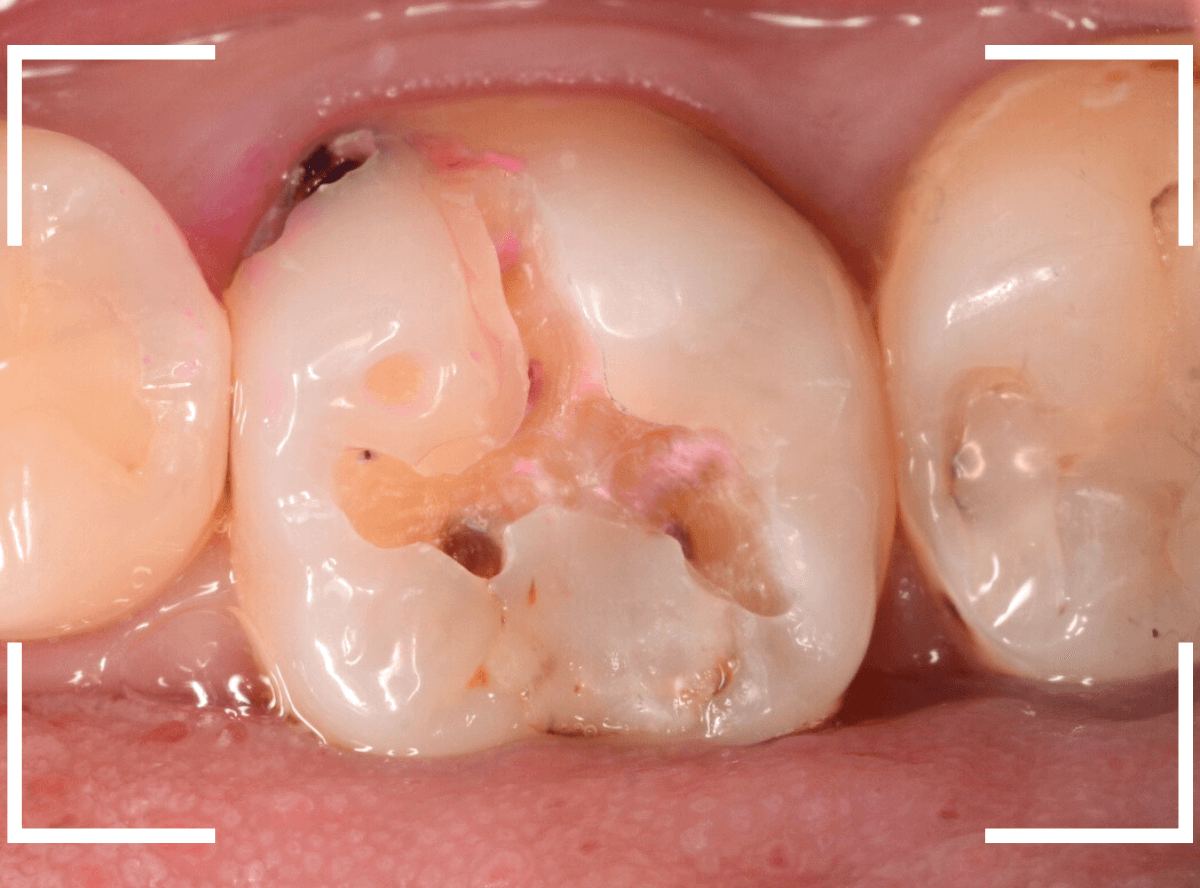

Case.18 虫歯なのは間違いないが、境界がはっきりしない

「つめものが外れて、噛むと痛い」という訴えで来院された患者さんさんです。

一見で、表面が虫歯になっているのと、レジンが劣化しているのがわかります。

レントゲン写真で確認します。

〇部が当該の歯です。

症状もあるので、虫歯が深そうですが、全体がもやっとして、どこからどこまで虫歯なのかはっきりわかりません。

まれに、こんな時もあります。

レジンを外し、虫歯の処置を進めます。

慎重に虫歯を除去し、一安心か、という寸前で(〇部、小さく出血しているところ)露髄してきました。

神経を除去しないとダメかもしれません。。。

神経を保護するお薬をつめて、経過観察します。

痛みが出ませんように。。。